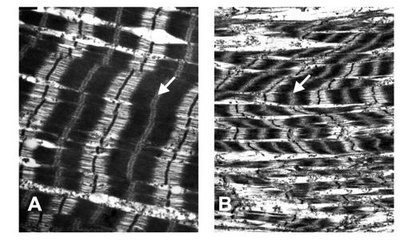

Pathology: Myocyte disarray, fibrosis, and abnormal sarcomere structure.